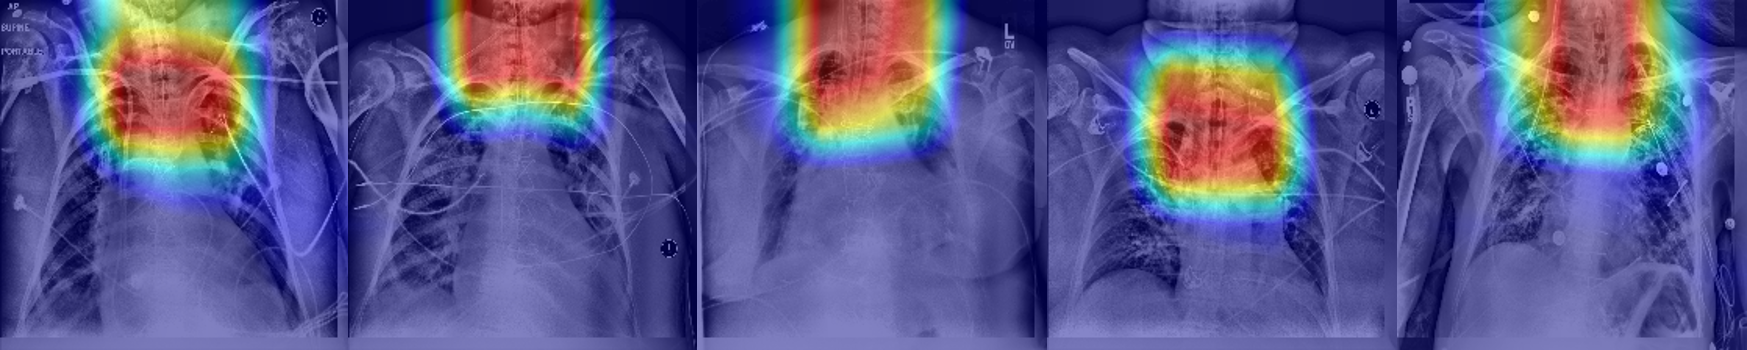

Figure 7: Heatmap examples using ET tube classification CNN

We conducted an additional experiment using a different CNN architecture only for the classification task: identification of the tubes in real case scenarios. We trained a DenseNet [10] architecture with the same dataset we used in the second phase of the combined model - real cases with and without ET tube (n=7944) for 50 epochs and Adam optimizer. Training only for classification using a large real training data, we reached a high accuracy with an AUC of 0.975. Figure 7 shows a heatmap visualization of the last convolutional layer of the network. This visualization clearly indicates the localization on the ET tube area.